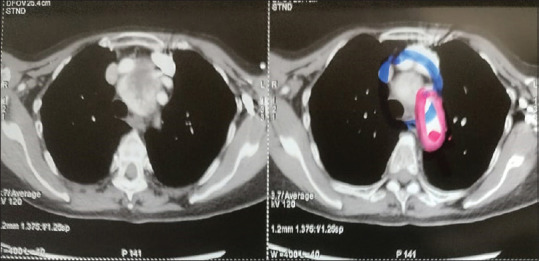

摘要:我们报告一例74岁女性胸骨后甲状腺肿大,接受视频辅助胸外科手术(VATS)进行左肺下叶切除术,需要单肺通气(OLV)。我们遇到了一个非常不寻常的并发症:对侧张力性气胸。手术开始45分钟后,突然发生了心血管衰竭。在确认双腔管的正确位置并排除纵膈肿块综合征(MMS)后,怀疑为紧张性气胸。立即穿刺减压后右胸管开胸术取得成功。本病例强调了在OLV期间突发心血管衰竭患者对侧张力性气胸保持高怀疑指数的重要性。

Abstract: We report a case of a 74-year-old female with a retrosternal goiter undergoing video-assisted thoracic surgery (VATS) for a left lung lower lobectomy, necessitating one-lung ventilation (OLV). We encountered a highly unusual complication: contralateral tension pneumothorax. Forty-five minutes into the surgical procedure, a sudden cardiovascular collapse occurred. After confirming the correct positioning of the double-lumen tube and excluding mediastinal mass syndrome (MMS), tension pneumothorax was suspected. Immediate needle decompression followed by right chest tube thoracostomy resulted in a successful patient outcome. This case highlights the importance of maintaining a high index of suspicion for contralateral tension pneumothorax in patients with sudden cardiovascular collapse during OLV.